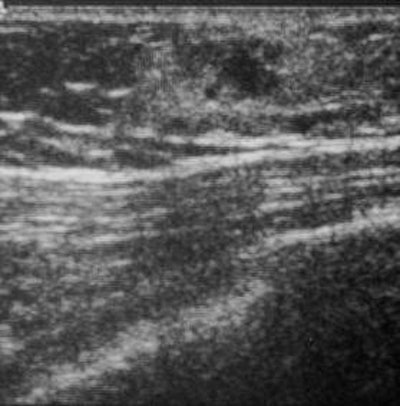

| Ultrasound reveals a lobulated, hypoechoic nodule with a microlobulated margin and an uneven echogenic boundary. The nodule is located in the subcutaneous layer. |

Traditional sonography revealed a lobulated, hypoechoic nodule with a microlobulated margin and an uneven echogenic boundary. Power Doppler ultrasound-guided core-needle biopsy, surgical excision, and a histologic exam revealed the hemangioma.